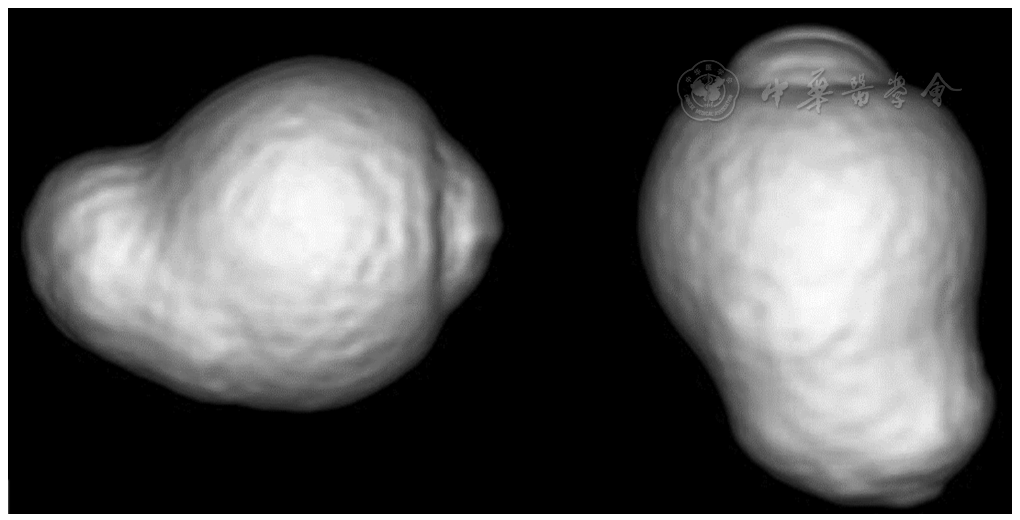

正如Spaide[79]所描述的,后巩膜葡萄肿是围绕后极部眼底区域的一种隆起,其曲率半径比相邻的眼球壁的曲率半径小(图5)[4,5]。后巩膜葡萄肿应与简单的巩膜向后弯曲区分,因为简单的巩膜后弓在高度近视眼的OCT中很常见。

Moriyama等最近利用三维(three-dimensional,3D)-MRI分析了整个眼的形状[5,101,102],这样即使是较大的后巩膜葡萄肿也可以完全成像(图6)。基于眼的3D-MRI图像发现,眼球形状的不同与威胁视力的病理性近视发展有关[5]。Ohno-Matsui[102]最近应用3D-MRI和广域眼底成像将后巩膜葡萄肿分为6种类型:宽黄斑型、窄黄斑型、视盘旁型、鼻侧型、下方型和其他型(图7)。这种分类是基于Curtin[103]之前将葡萄肿分为的10种类型,其中Ⅰ~Ⅴ型是原发型葡萄肿,Ⅵ~Ⅹ型是复合型葡萄肿。最主要的葡萄肿类型是宽黄斑型(占葡萄肿的74%),其次是窄黄斑型葡萄肿(占葡萄肿的14%)。然而,把3D-MRI作为一种筛查手段并不可行,由于相对低的空间分辨率,浅层葡萄肿的细微变化难以被发现。

最近已经开发出一种新的广域扫频OCT系统的原型机,使用多条扫描线生成扫描图,允许对23 mm×20 mm大小感兴趣区域和5 mm深处进行后巩膜葡萄肿的三维重建。Shinohara等[104]发现,广域OCT可以提供迄今为止最大分辨率和范围的后巩膜葡萄肿的断层图像,并可能取代3D-MRI评估后巩膜葡萄肿。广域OCT显示葡萄肿边缘一致性的变化,表现为从视网膜周边到葡萄肿边缘脉络膜逐渐变薄,再从葡萄肿边缘向后极部逐渐增厚,并伴有葡萄肿边缘巩膜曲率半径的改变(图8)。